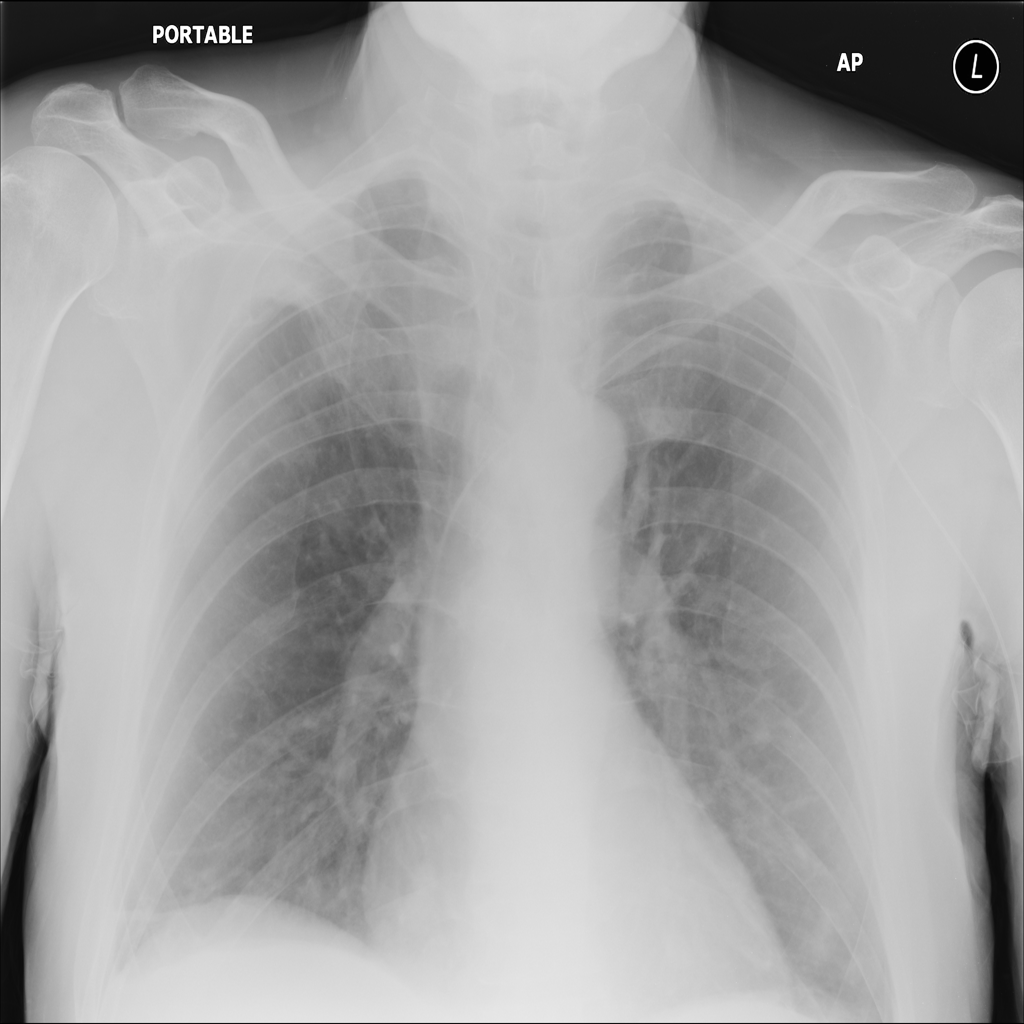

Nodule

A nodule is a small rounded opacity in the lung or chest field. It is a descriptive imaging finding that can be benign or more concerning depending on size, appearance, and context.

Showing up to 90 reference images for Nodule.

PAT-250B · IMG-000Nodule

PAT-250B · IMG-000

PA